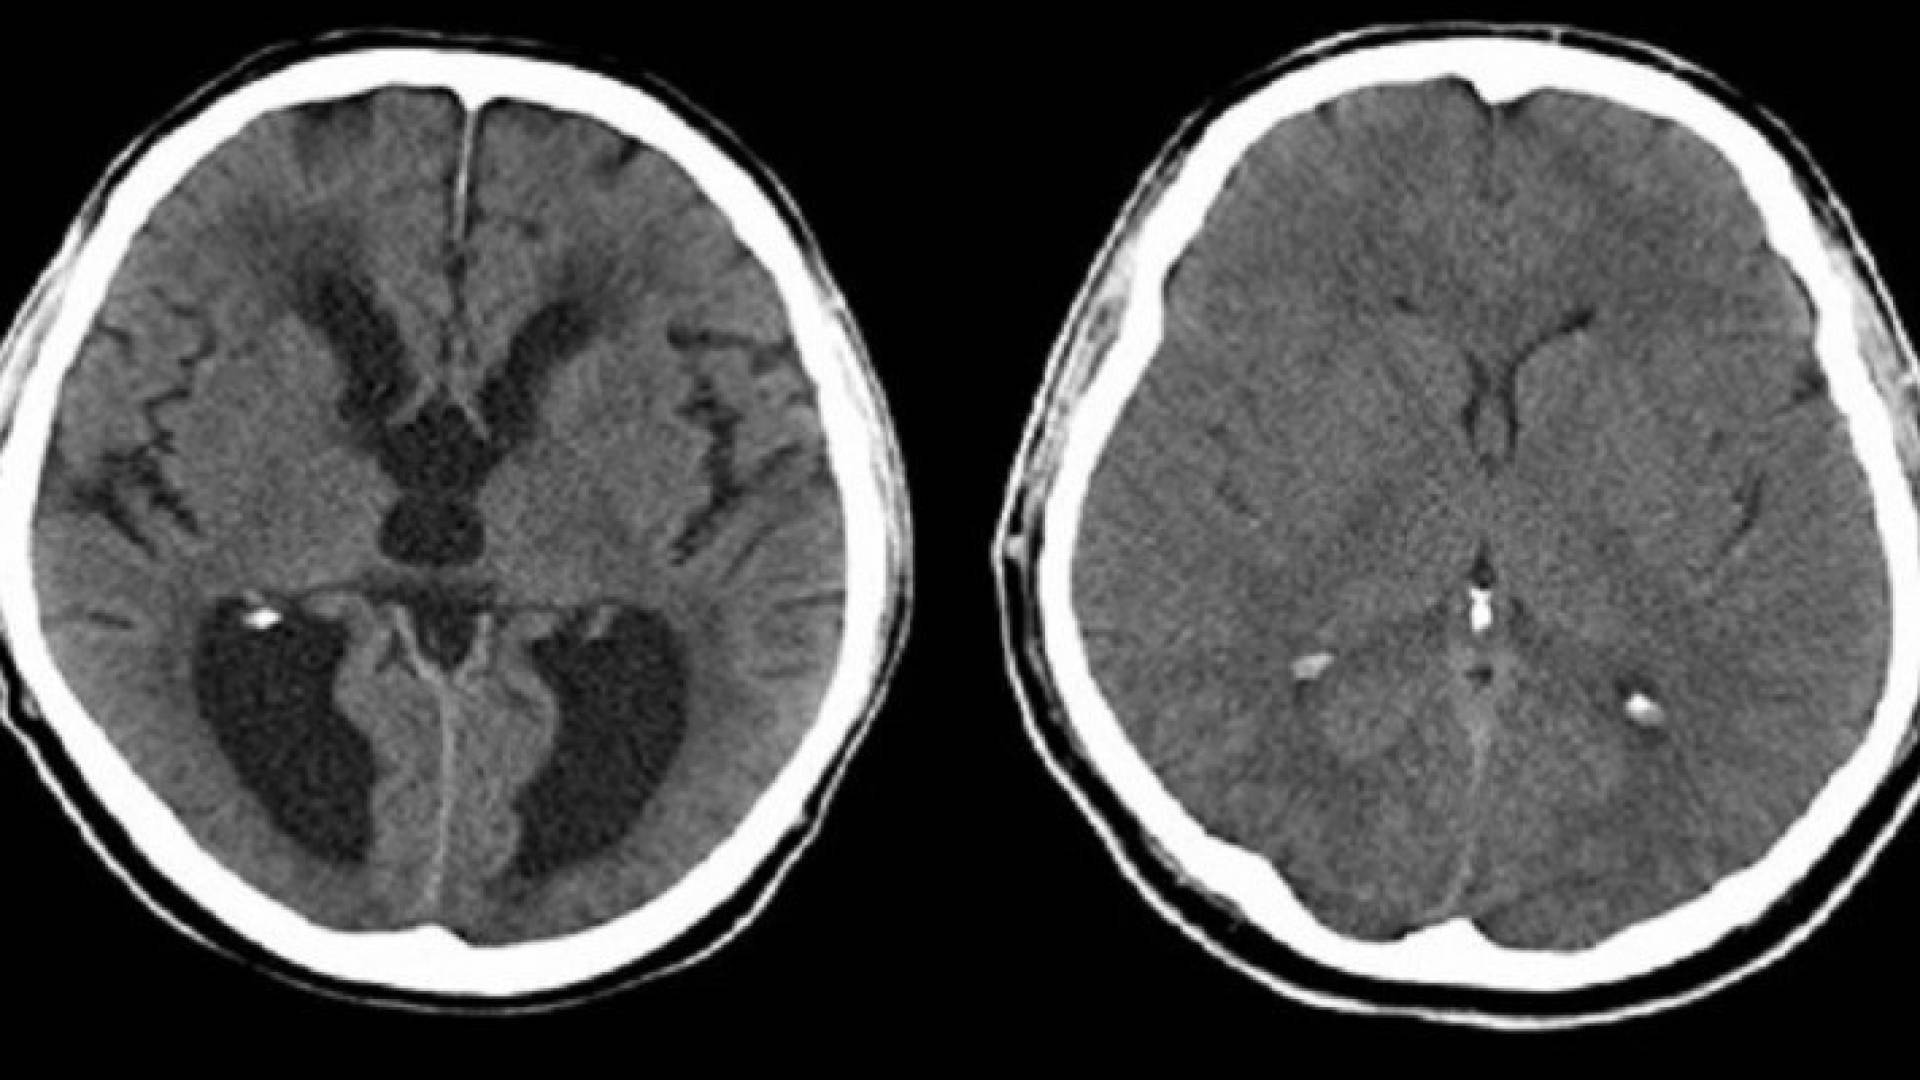

توصل علماء من الولايات المتحدة إلى نتائج جديدة حول أسباب استسقاء الرأس أو ما يعرف بتراكم السائل الدماغي في تجاويف وجيوب دماغ المواليد الجدد.

وأكد العلماء أن التجارب على الفئران أظهرت أيضا أن "الاستسقاء الرأسي" التي تصاب به القوارض سببه مشاكل في الخلايا "البطانية" لبعض تجاويف الدماغ ما يؤدي إلى تراكم السوائل في تلك التجاويف، ومشاكل الخلايا تلك يعود سببها إلى فقدان بروتين SNX27.